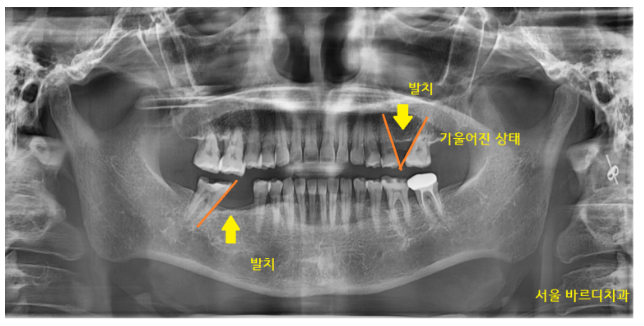

강동구 치과에 방문해 주신 환자분입니다.

치아가 많이 쓰러져 있는 것이

뽑고 시간이 많이 흐른 것으로 보았습니다.

윗니 어금니 1개

아래 어금니 1개

총 2개가 발치된 상황이네요.

"어머니, 뽑힌지 오래되셨나 봐요~

치아가 많이 쓰러졌네요. "

우선 구강을 살펴보았는데요.

230713

윗니 어금니는 발치한지 오래되어

공간이 거의 없었습니다.

치아가 제자리를 벗어나 크게 움직인 탓이죠~

임플란트 대신 브릿지 치료가 적합해 보였습니다.